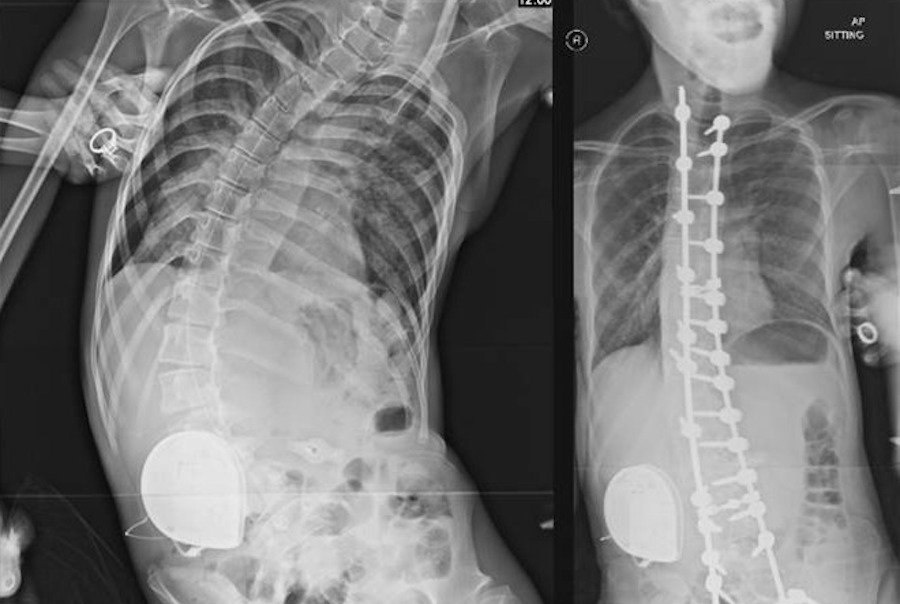

Постуральный коллапс — состояние, при котором тело постепенно теряет способность сохранять симметричное и устойчивое положение. Оно не возникает внезапно, а развивается медленно, порой годами, особенно у людей, которые большую часть дня проводят сидя или лежа.

Постоянное скручивание, сжатие грудной клетки и таза нарушают дыхание, работу сердца и пищеварения. Исправить ситуацию можно — если вовремя заметить проблему и выстроить систему постурального менеджмента.